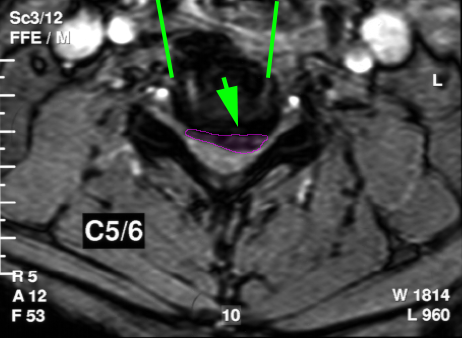

Πρόσθια αυχενική μικροχειρουργική δισκεκτομή σε ασθενή με αυχενική δισκοκήλη. Η τραχεία (πράσινο), ο οισοφάγος (κίτρινο) παρεκτοπίζονται αριστερά (κόκκινα βέλη) και για να δημιουργηθεί το κανάλι προσπέλασης στον δίσκο (κυανές γραμμές). Ο δίσκος αφαιρείται και κατόπιν εξαιρείται και η δισκοκήλη(μωβ). Οι καρωτίδες είναι οι δύο κόκκινοι κύκλοι εκατέρωθεν της προσπέλασης.